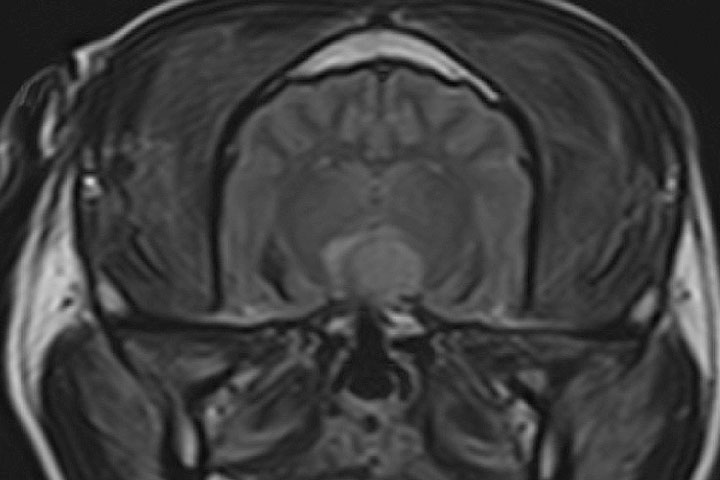

Meningioma

It is the most common primary brain tumour in dogs and cats. Meningiomas are extra-axial, well demarcated, large masses. As derived from the leptomeninges, they sit between the dura and the brain.

On MRI, they appear as well defined, homogeneous, broad base masses with strong and uniform contrast enhancement.

The majority of meningiomas are supratentorial (75%), but caudal fossa or skull base meningiomas are occasionally seen.